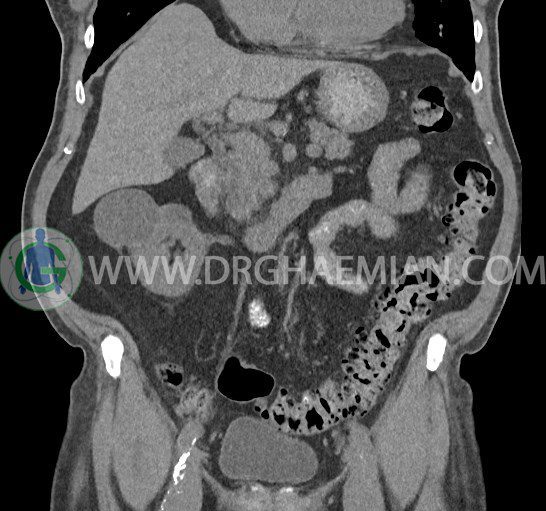

سی تی اسکن لگن یکی از روش های تصویربرداری با سی تی اسکن است. این روش با استفاده از تشعشعات تصاویر عرضی از ناحیه شکمی ایجاد میکند. در این کیس ديورتيكولوزيس، کیست های کورتیکال در هر دو کلیه، لنفادنوپاتی، کلسیفیکاسیون دیواره آئورت و شریان ایلیاک، تغییرات DJD ناحیه توراکولومبار و پروستات بزرگتر از عادی دیده می شود.

در سي تي اسکن اسپيرال شکم و لگن با و بدون کنتراست خوراکی و وريدی (مولتي ديدکتور 16 با مقاطع ظريف و بازسازي هاي ساژيتال و کرونال):

– ديورتيكولوزيس در کولون نزولي وسيگموئيد

لنفادنوپاتي به ابعاد mm 22 x 25 مجاور شريان ايلياک خارجي چپ و به ابعاد mm 17 x 28 مجاور شريان ايلياک خارجي راست

– تغييرات DJD در ناحيه توراکولومبار و

– پروستات به ابعاد mm 45 x 54، بزرگ تر از نرمال

مشهود است.